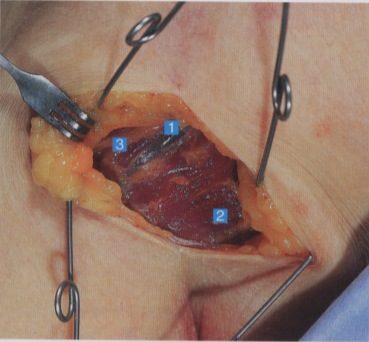

牵开头静脉,可见内侧的胸大肌、外侧的三角肌,以及覆盖肱二头肌短头的筋膜

切开筋膜,显露出肱二头肌短头

1. 头静肌;2. 胸大肌;3. 三角肌;

4. 肱二头肌筋膜;5. 肱二头肌短头;